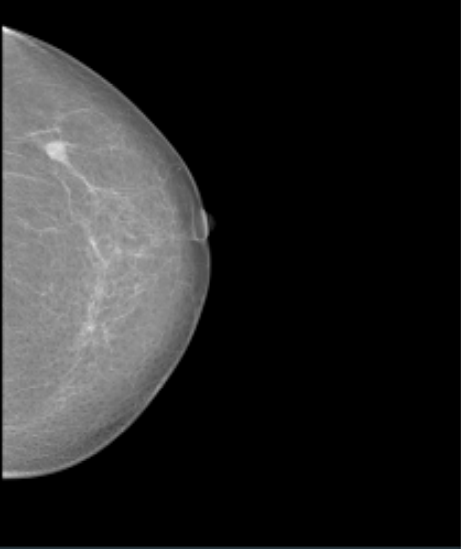

Datos Clínicos: Paciente Femenino de 44 años.

Diagnóstico: Calcificación Anormalidad Sospechosa.

Dimensiones: 632 x 548.